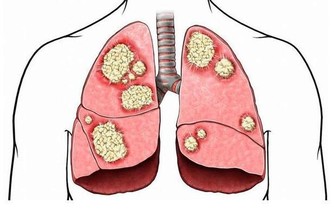

醫學上,胰腺癌是一種惡性程度很高,診斷和治療都很困難的消化道惡性腫瘤,約90%為起源於腺管上皮的導管腺癌。其發病率和死亡率近年來明顯上升。5年生存率<1%,是預後最差的惡性腫瘤之一,正因如此,人們將其稱為癌症之王!胰腺癌早期的確診率不高,手術死亡率較高,而治愈率很低。本病發病率男性高於女性,男女之比為1.5~2:1,男性患者遠較絕經前的婦女多見,絕經後婦女的發病率與男性相仿。

胰腺癌的病因尚不十分清楚。但大量的流行病學數據顯示,它的發生與吸煙、飲酒、高脂肪和高蛋白飲食、過量飲用咖啡、環境污染及遺傳因素有關;近年來的調查報告發現糖尿病人群中胰腺癌的發病率明顯高於普通人群;也有人注意到慢性胰腺炎病人與胰腺癌的發病存在一定關係,發現慢性胰腺炎病人發生胰腺癌的比例明顯增高;另外還有許多因素與此病的發生有一定關係,如職業、環境、地理等。